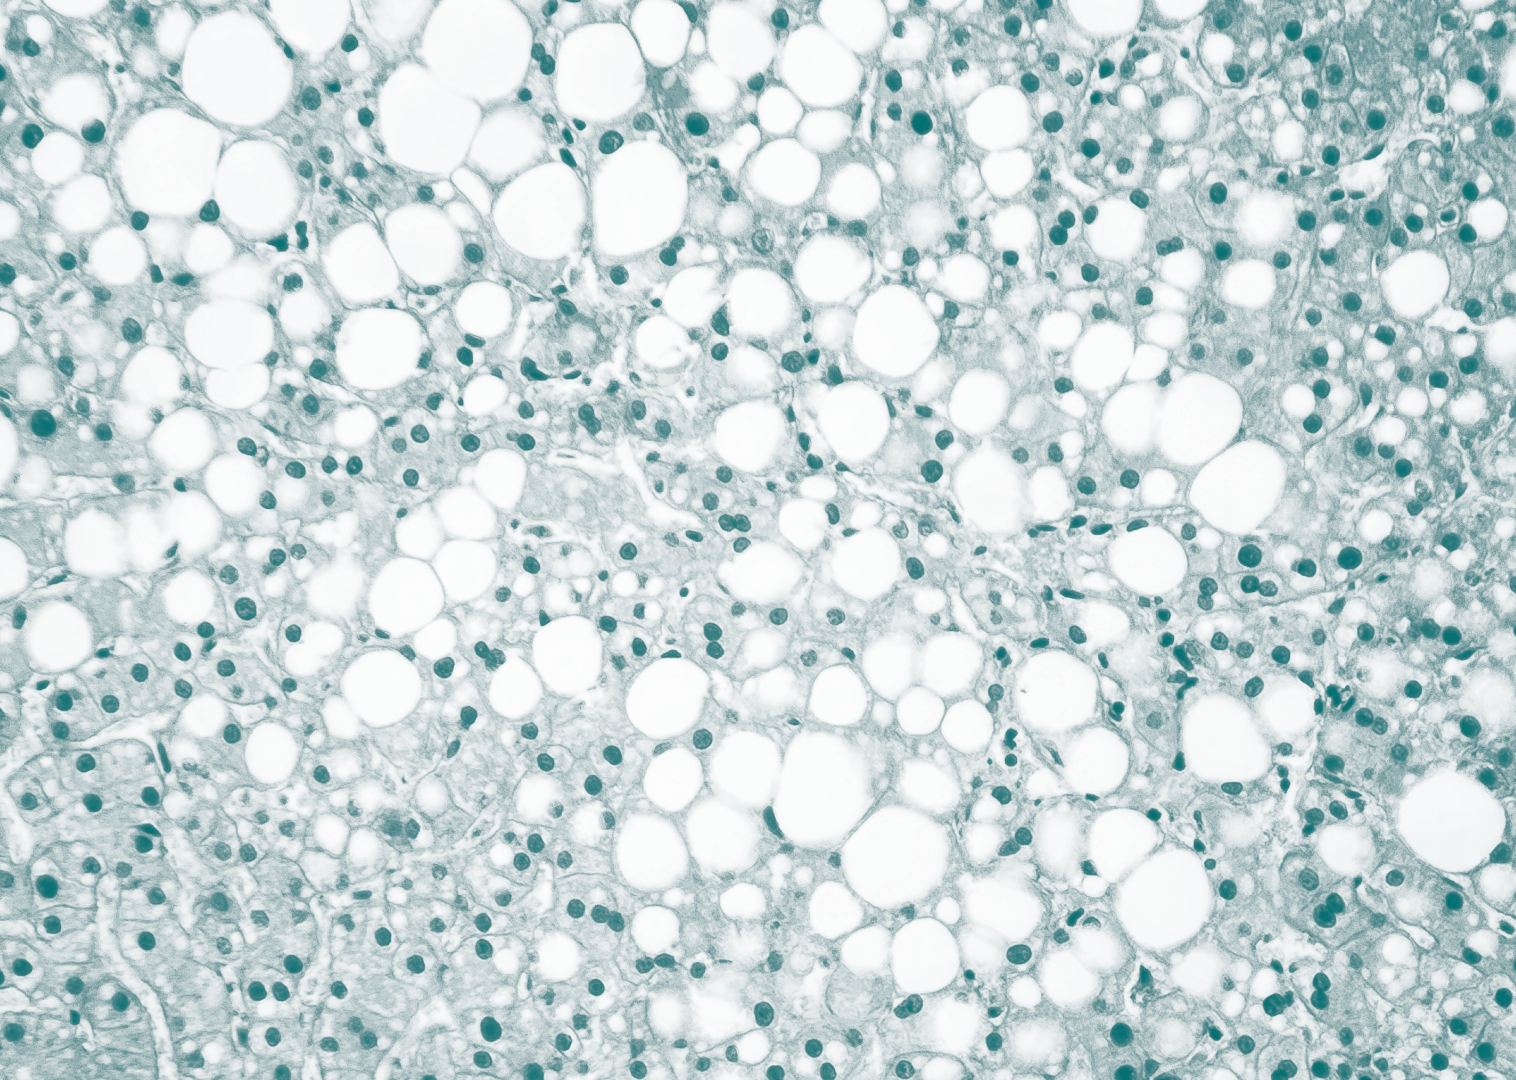

Am 12. Juni fand der globale Fettleber-Tag statt. Das Ziel seit 2018: Das öffentliche Bewusstsein für die Dringlichkeit sogenannter Steatotischer Lebererkrankungen (SLD) schärfen. Denn SLD und ihre Spätfolgen sind laut dem Global Liver Institute „eine verborgene globale Epidemie“, welche bis 2030 schätzungsweise 357 Millionen Menschen betreffen wird. Schon heute sind es laut der Deutschen Leberhilfe 20 bis 30 Prozent der Bevölkerung in den Industrienationen. Die Krux: Die Leber leidet still. „Die Symptome sind sehr unspezifisch: Müdigkeit, Abgeschlagenheit, Konzentrationsstörung“, zählt Professor Stephan Kanzler, Chefarzt der Medizinischen Klinik2 am Leopoldina-Krankenhaus in Schweinfurt, auf. Erst in fortgeschrittenen Stadien würden dem Internisten zufolge Bauchschmerzen oder Komplikationen wie Bauchwasser oder Blutungen auftreten. Doch was ist eine Fettleber? „Sie entsteht, wenn sich überflüssige Kalorien – vor allem aus Zucker und Fett – in der Leber ablagern.“ Der „harmlose“ Beginn: Die Leberzellen (Hepatozyten) nehmen Fetttröpfchen auf, die der Körper nicht mehr verarbeiten kann. Die Leber, durch die jede Minute rund eineinhalb Liter Blut fließen, wird zum Speicherort. In Industrieländern ist der häufigste Auslöser ein ungesunder Lebensstil. Professor Kanzler fasst zusammen: „Die üblichen Verdächtigen sind Bewegungsarmut, Übergewicht und Diabetes Mellitus Typ 2.“ Denkbar seien auch Begleiterscheinungen anderer Erkrankungen wie Zöliakie oder Medikamente wie unter anderem Tetrazykline. Darüber hinaus könnten genetische und hormonelle Einflüsse eine Rolle spielen. Auch Alkohol sei ein Risikofaktor – schon geringe Mengen könnten langfristig die Leber schädigen. Die Erkrankung entwickelt sich schleichend und in mehreren Stadien. Der Arzt beschreibt die Bandbreite: „Von der einfachen Fettleber (Steatose) über die Fettleberentzündung (Steatohepatitis) bis hin zum Endorganschaden – sprich Leberfibrose und -zirrhose.“ Während die einfache Fettleber häufig reversibel sei, könne eine entzündete und vernarbte Leber lebensbedrohlich werden, warnt der Gastroenterologe. Mit bildgebenden Verfahren in der Diagnostik lasse sich nicht nur der Fettgehalt, sondern auch die Gewebeelastizität gut bestimmen – beides seien wichtige Hinweise auf den Krankheitsverlauf. Biopsien seien kaum mehr nötig. Aber wie das Ruder herumreißen? „Am Anfang steht die Information über die Zusammenhänge und eine vernünftige Ernährungsberatung“, so Professor Kanzler. Wer konsequent Gewicht reduziere – etwa durch mediterrane Ernährung oder Intervallfasten – könne die Leberverfettung deutlich zurückdrängen. Auch Kaffee zeige laut Studien positive Effekte. Daneben kämen auch Medikamente zum Einsatz. Präparate wie Semaglutid oder neu entwickelte Wirkstoffe wie Resmetirom zielten auf die Reduktion der Leberfettmenge ab und würden auch bei entzündlichen Verläufen helfen. Dennoch bliebe die nachhaltigste Methode die eigene Verhaltensänderung. „Die Heilungschance ist gegen 100 Prozent“, betont Professor Kanzler mit Blick auf frühe Stadien der Erkrankung. Sei die Leber bereits vernarbt, könnten Schäden dauerhaft bleiben und im schlimmsten Fall eine Transplantation notwendig machen. Der Arzt stellt daher abschließend klar: „Die Fettleber ist keine Bagatelle, sondern eine still wachsende Gefahr – oft über Jahre unbemerkt. Mittlerweile hat sie sich zur häufigsten Ursache für Lebertransplantationen in westlichen Ländern entwickelt.“ Umso wichtiger sei es, rechtzeitig gegenzusteuern. Denn: „Kaum eine andere chronische Erkrankung ist so gut beeinflussbar.“